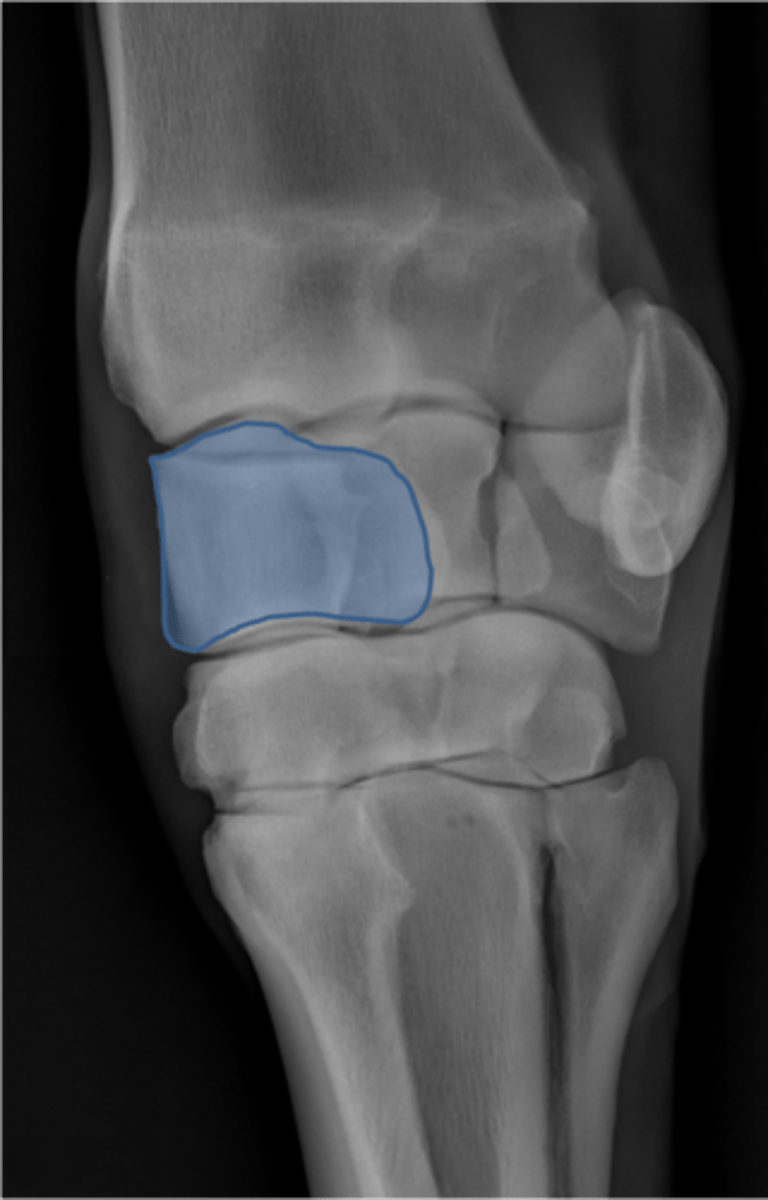

Carpus, lateral

ID joint and view

Antebrachiocarpal joint

Middle carpal joint

Carpometacarpal joint

Radial carpal bone

Intermediate carpal bone

Ulnar carpal bone

Third carpal bone

Second carpal bone

Fourth carpal bone

Accessory carpal bone

Second metacarpal (medial splint)

Fourth metacarpal (lateral splint)

Cannon bone